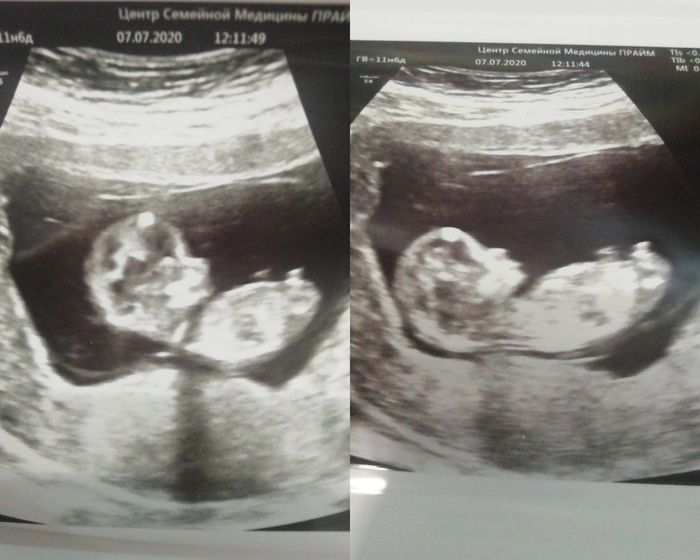

Узист сказал это не нога. Но может быть как девочка, так и мальчик. Мол рано ещё)

Что думаете?)

Мальчик если сравнивать по фото из интернета.

Мальчик, судя по фото с интернета

Вот, а я судя по фото с интернета подумала девочка)

Присмотрелась, да, похоже на мальчика

У нас было как у вас, мальчик